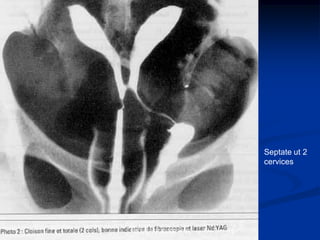

Septate ut 2

cervices